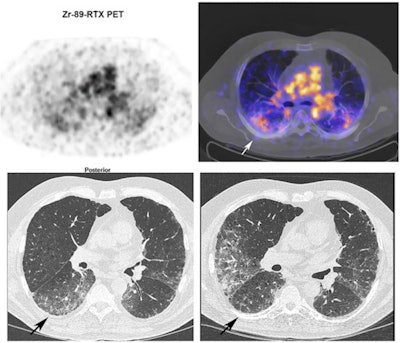

Zr-89 rituximab PET/CT and HRCT of a 65-year-old patient with fibrotic nonspecific interstitial pneumonia-associated rheumatoid arthritis (case 3). Zr-89 rituximab PET (top left) axial PET image (top right) fused Zr-89 rituximab PET/CT. HRCT (bottom left) at baseline of PET and HRCT after one year (bottom right). Matching of the axial view between the PET/CT and HRCT is not exactly possible since the HRCT is performed with an inspiration command and the PET/CT is in the resting state. The Zr-89 rituximab activity is more focused in the lower lobes. This central area on Zr-89 rituximab correlates more with the HRCT ground glass; see, for example, the right lower lobe ground-glass area. The HRCT after one year post rituximab did not show any ground glass in this area. However, new ground-glass areas emerged on the HRCT in the lower upper lobes. The patient remained stable in pulmonary function. Image courtesy of the European Journal of Nuclear Medicine and Molecular Imaging through CC BY 4.0.Then, prior to and six months after treatment, the researchers compared the radiotracer uptake with pulmonary function tests (PFT) such as forced vital capacity (FVC), which were used to classify patients as reponders or nonresponders.

Fifteen patients (71%) were classified as responders. Pulmonary Zr-89 rituximab PET SUVmean was significantly correlated with change in patient FVC (K = 0.49) when using target-to-background ratios, but not when using SUVmean alone, the researchers found. In addition, Zr-89 rituximab SUVmean was significantly higher in responders than in nonresponders, according to the findings.